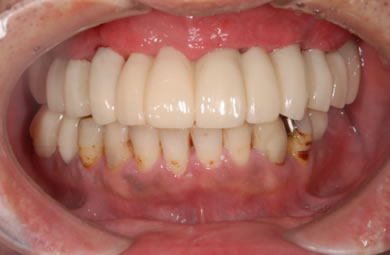

| 治療方針 | 骨再生療法にて上顎の骨を増やしインプラント治療にて審美的・機能的回復を行う。 | ||||||||||||||||||||||||||||||||

| 治療内容 | インプラント7本(ソケットリフト)、ハイブリッドセラミック12本 | ||||||||||||||||||||||||||||||||

| 総治療費 | 3,207,924円 | ||||||||||||||||||||||||||||||||

| 治療期間 | 1年6ヶ月 |